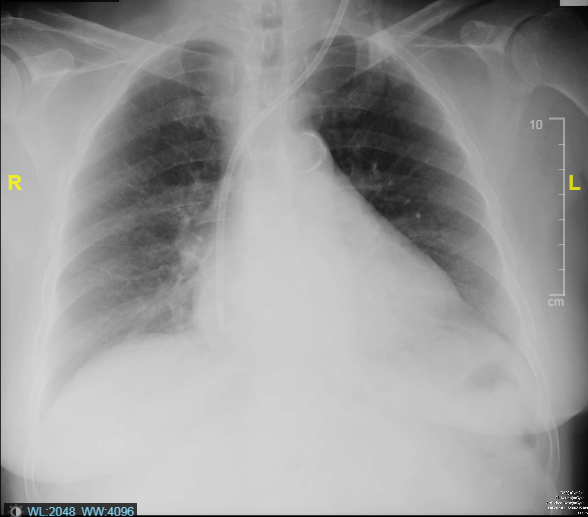

Relevant Test Results Prior to Catheterization

The initial electrocardiogram indicated sinus rhythm and normal axis without Left Ventricular Hypertrophy (LVH). No changes in the ST segment or T wave were noted. High-sensitivity troponin levels were serially elevated, suggesting Myocardial Infarction (MI). The echocardiography, however, showed no regional wall motion abnormality (RWMA) with preserved Left Ventricular systolic function (Ejection Fraction 55%). All cardiac valves were normal with no evidence of stenosis or regurgitation.